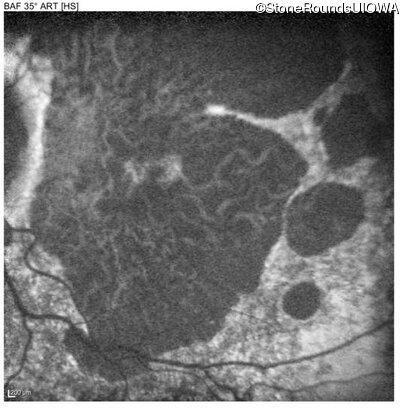

Blue Autofluorescence - Left - 20/40 +2

Exemplar